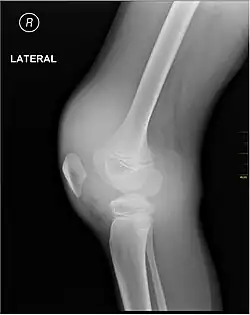

-

X-ray of Hemarthrosis -

X-ray of Hemarthrosis